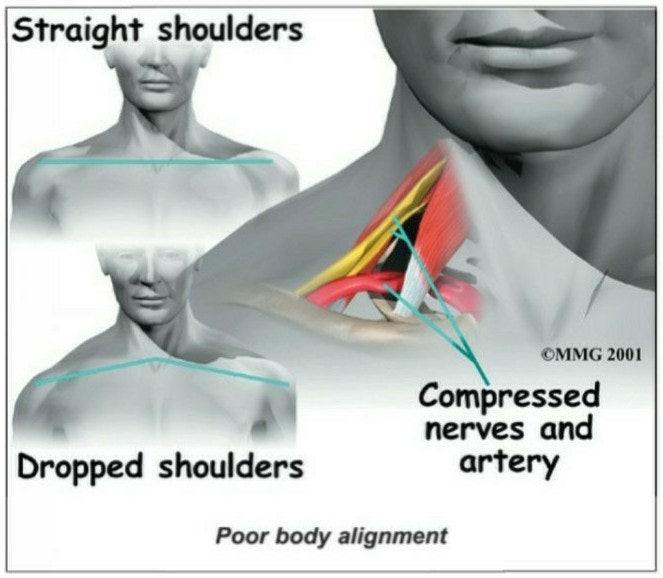

그 이유는 네 번째, 다섯 번째 손가락은 체형과 체질의 중심이기 때문입니다.이 발가락이 어긋나면 온몸이 어긋나요.

그렇기 때문에 네 번째 손가락이 무너지면 체형이나 체질이 무너집니다.